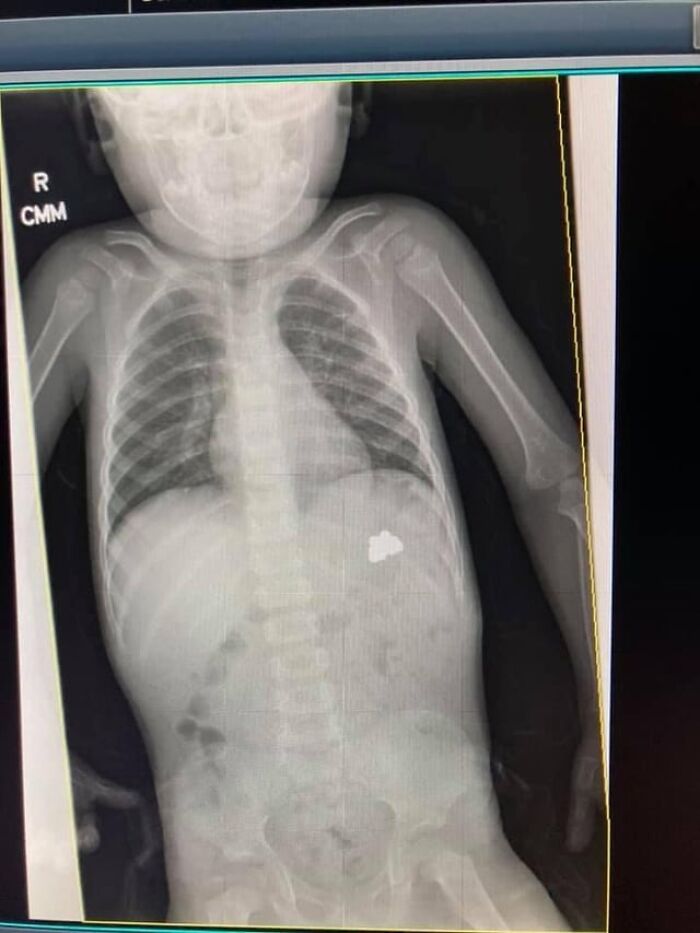

My 9-Year-Old Broke Her Arm. Doc Said She’ll Be Fine, But Should I Worry?